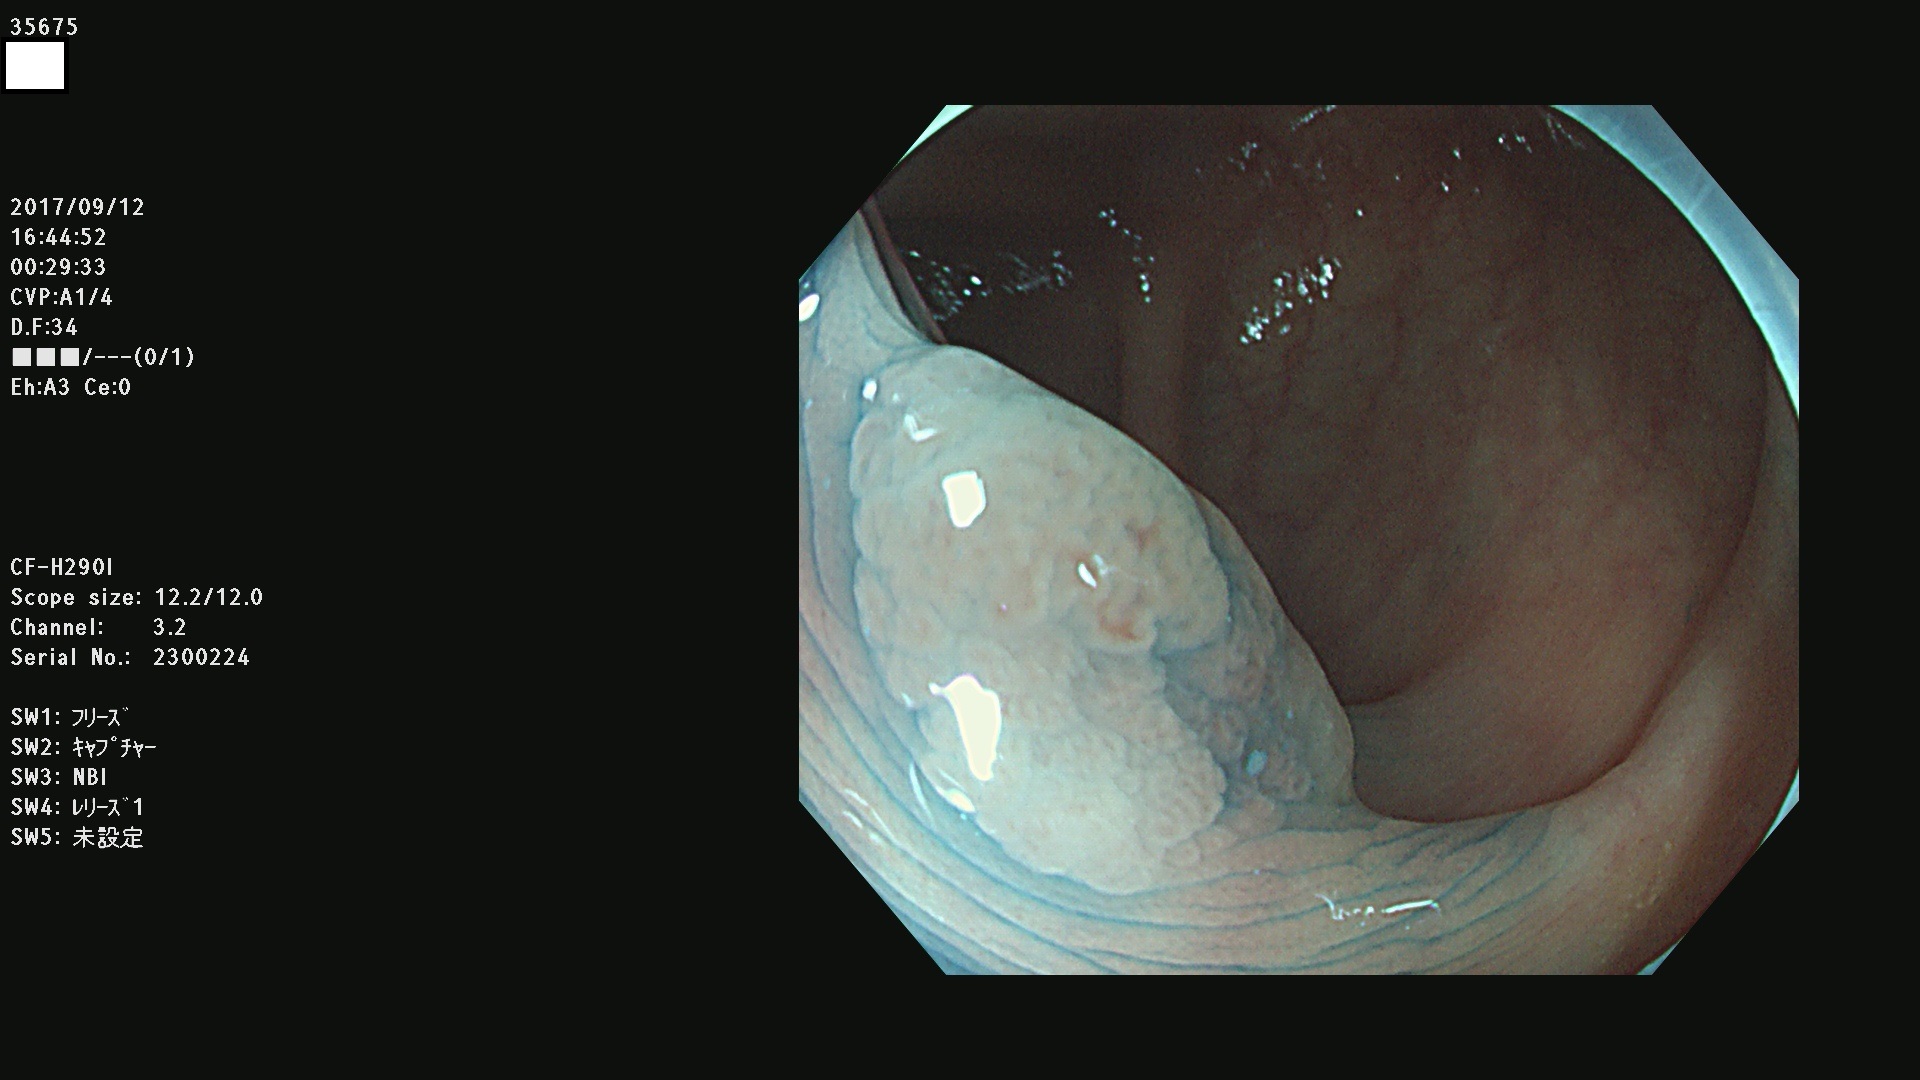

発見困難で危険性の高い平坦型病変(上記100名より抽出)

35600 35603 35604 35609 35612 35613 35614 35619(SSA/Pのみ) 35624 35625 35626 35627 35629 35630 35631 35633 35634 35635 35636 35638 35641 35642 35643 35644 35645 35646(SSA/Pのみ) 35648 35651(SSA/Pのみ) 35652 35653 35655 35656(SSA/Pのみ) 35659 35660 35664 35665 35667 35668 35669 35670 35671 35675 35678 35679 35680 35682 35684 35689(SSA/Pのみ) 35695 35696 35699